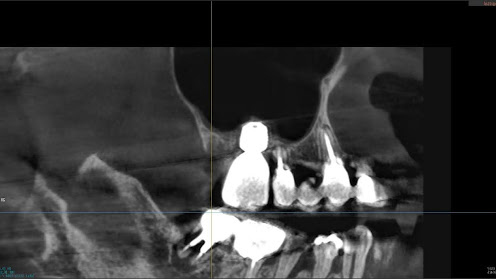

3.左上5の頬・舌側の大幅な骨欠損と上顎既存骨3mmまでの骨欠損がおこった症例に対しておこなったインプラント治療

Before

枚方市のインプラントの症例

I・K 様 女性 40代

症状としては、左上5の歯根破折を起こしていたため、排膿と自発痛をみとめた。それにともなう骨の大きな欠損。

治療法としては、炎症が強くたったためと、炎症による頬側側歯肉の退縮を認めていたために、まず、抜歯を行い上顎洞内及び歯抜した周囲組織の回復を試みた。その後、患者様がインプラント治療を希望したため、薄い上顎骨に対しては、グラフトレスサイナスリフト、骨欠損部には、人口骨補填を行い、頬側歯肉が退縮していることを改善するために、1回法でリーリングアバットメントを装着して、アバットメントの上に歯肉が覆うようにして、歯肉のボリューム回復を行った。2か月後、インプラントが骨と結合していることを確認して、光学印象を行い、2週間後にアバットメントとジルコニアクラウンを装着した。

治療結果としては、大幅な骨欠損があったが、グラフトレスサイナスリフトと骨欠損部に人工骨を補填して、抜歯した穴が自然に治る状態にしたことで、2か月半という短い期間での治療を完了することができた。(仮に、GBRや通常のサイナスリフトでの治療を行っていたら、最低でも1年は、かかってくる治療であると考える。)また、今回は、即時荷重を避け、1回法での治療を行ったことで、噛めない期間ができてしまったが、1回法で行ったことにより、歯肉のボリュームが増して、ブラッシングがしやすい口腔内環境にすることができた。低侵襲で、短時間で、治療を終えることができ、また、審美性・機能性の回復も行えたことができた。

治療の期間・回数:約2.5か月、6回

治療の価格:368,500円(税込)

治療費の内訳:インプラント基本料(フィックスチャー及び手術費用、投薬費用、レントゲン費用、インプラント上部費用(アバットメントおよびジルコニアクラウンの費用用)330000円(税込み)。オプション費用グラフトレスサイナスリフト費用プラス人工骨費用 38500円(税込み

治療のリスクや副作用:手術後に、痛みや腫れ、出血、合併症などを引き起こす可能性があります。噛む感覚がご自身の歯と異なる場合があります。見た目がご自身の歯と異なる場合があります。手術後にメインテナンスを継続しないと、インプラントが抜け落ちる可能性があります。